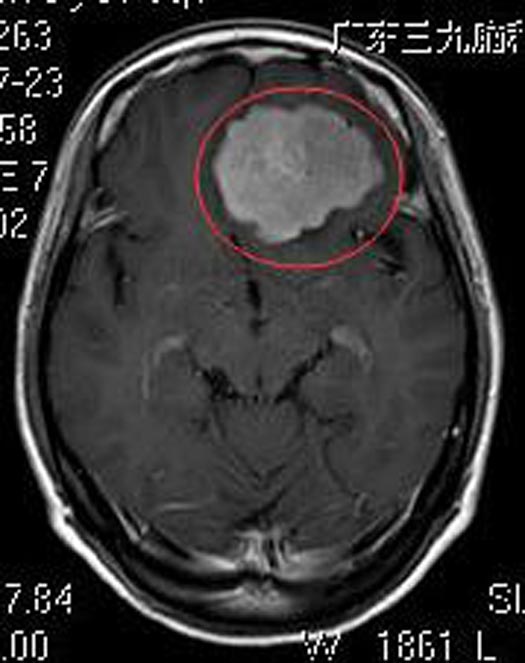

知道检查结果,儿女们吓出一身冷汗,赶紧陪着母亲来到广东三九脑科医院。进一步头颅MR 检查显示:前颅窝底左侧占位病灶,病灶范围约53.2mm×37.8mm×43.1mm,考虑脑膜瘤可能性大。

家属要求手术治疗,经评估无手术禁忌症。综合神经外科鲁明主任主刀,在全麻下行冠状开颅左侧蝶骨平台脑膜瘤切除术,术中显微镜下见肿瘤呈灰白色,鱼肉状,质韧,边界较清,血供丰富,予镜下将肿瘤顺利全切除。术后病理结果提示:砂粒体型脑膜瘤 WHO I级。